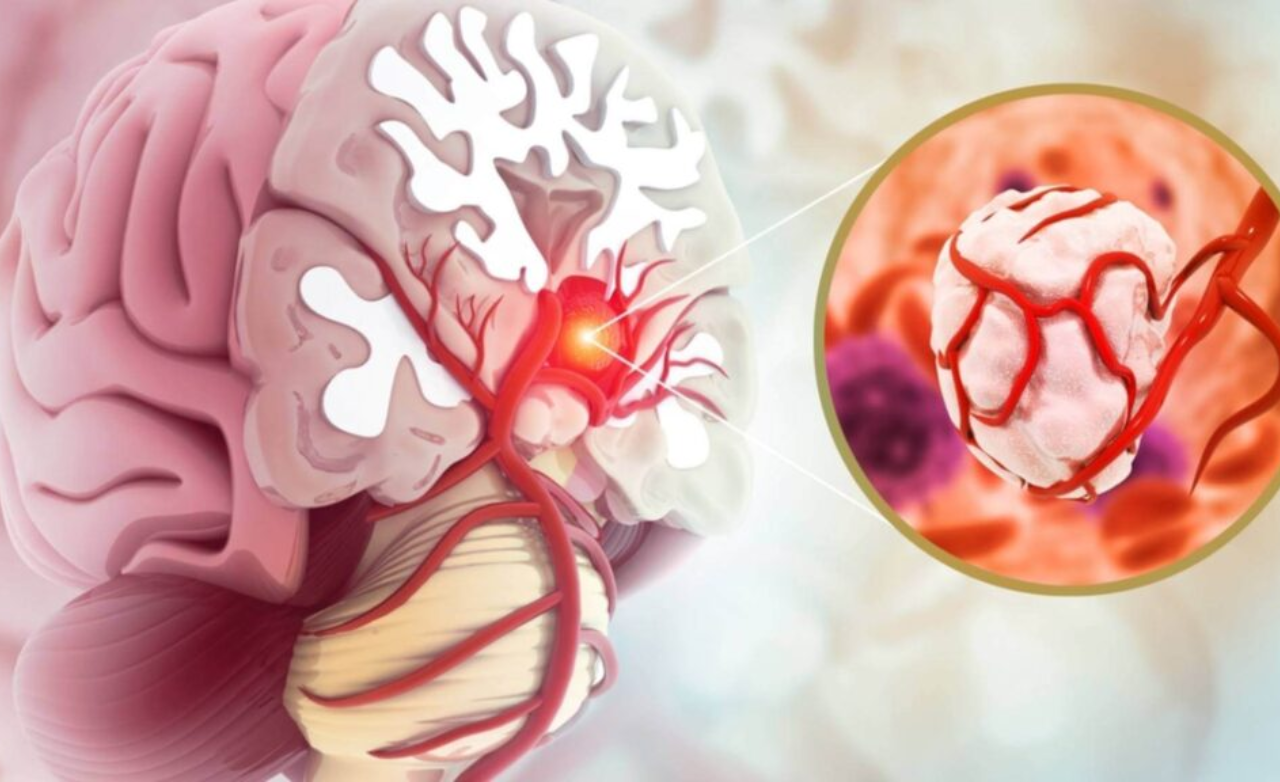

Flow diverter treatment is a minimally invasive procedure used to treat complex brain aneurysms that are difficult to manage with surgery or coiling. It is commonly recommended for wide-neck or hard-to-reach aneurysms.

A special device is placed inside the parent artery to redirect blood flow away from the aneurysm, allowing it to heal naturally while maintaining normal brain circulation.

Stent or balloon assisted coiling is used for wide-neck brain aneurysms where simple coiling is unsafe or insufficient. These techniques support the aneurysm neck during treatment.

They help keep coils securely in place, prevent coil movement, and improve long-term aneurysm sealing safely.

Intrasaccular devices are placed directly inside the aneurysm sac to block blood flow at its origin. They are useful for select wide-neck aneurysms.

These devices seal the aneurysm internally without affecting the parent artery or surrounding brain circulation.